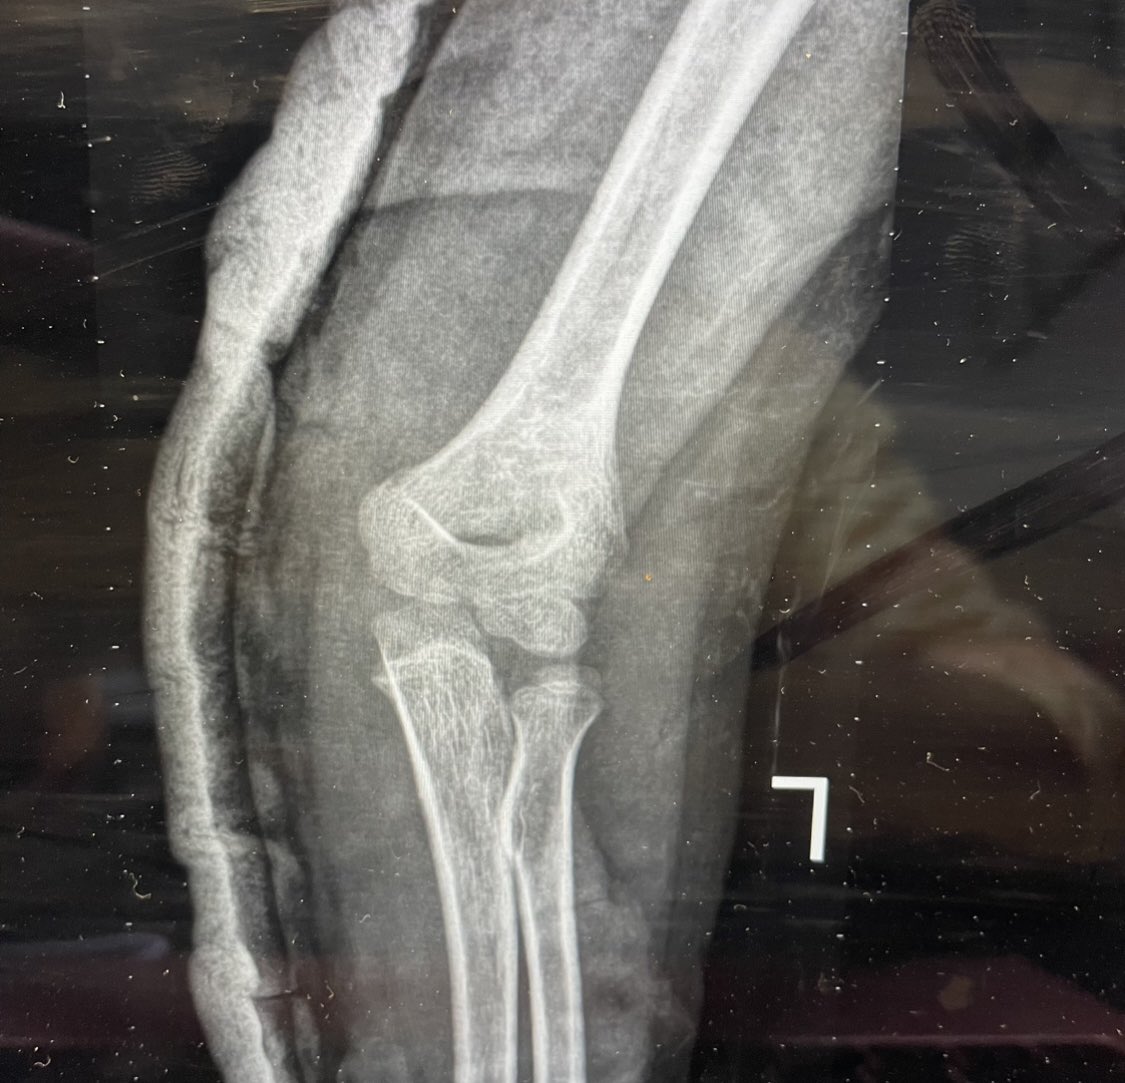

58 male fall from height last week !

Hx: HTN , CAD

Medicine :Aspirin 81 , Clopidogrel

When I aspirate hematoma there was about 6 ml blood

this is the pre_after reduction and the follow up today

He is not elderly in shape and body he looks like 40 !

1/2

@#orthotwitter